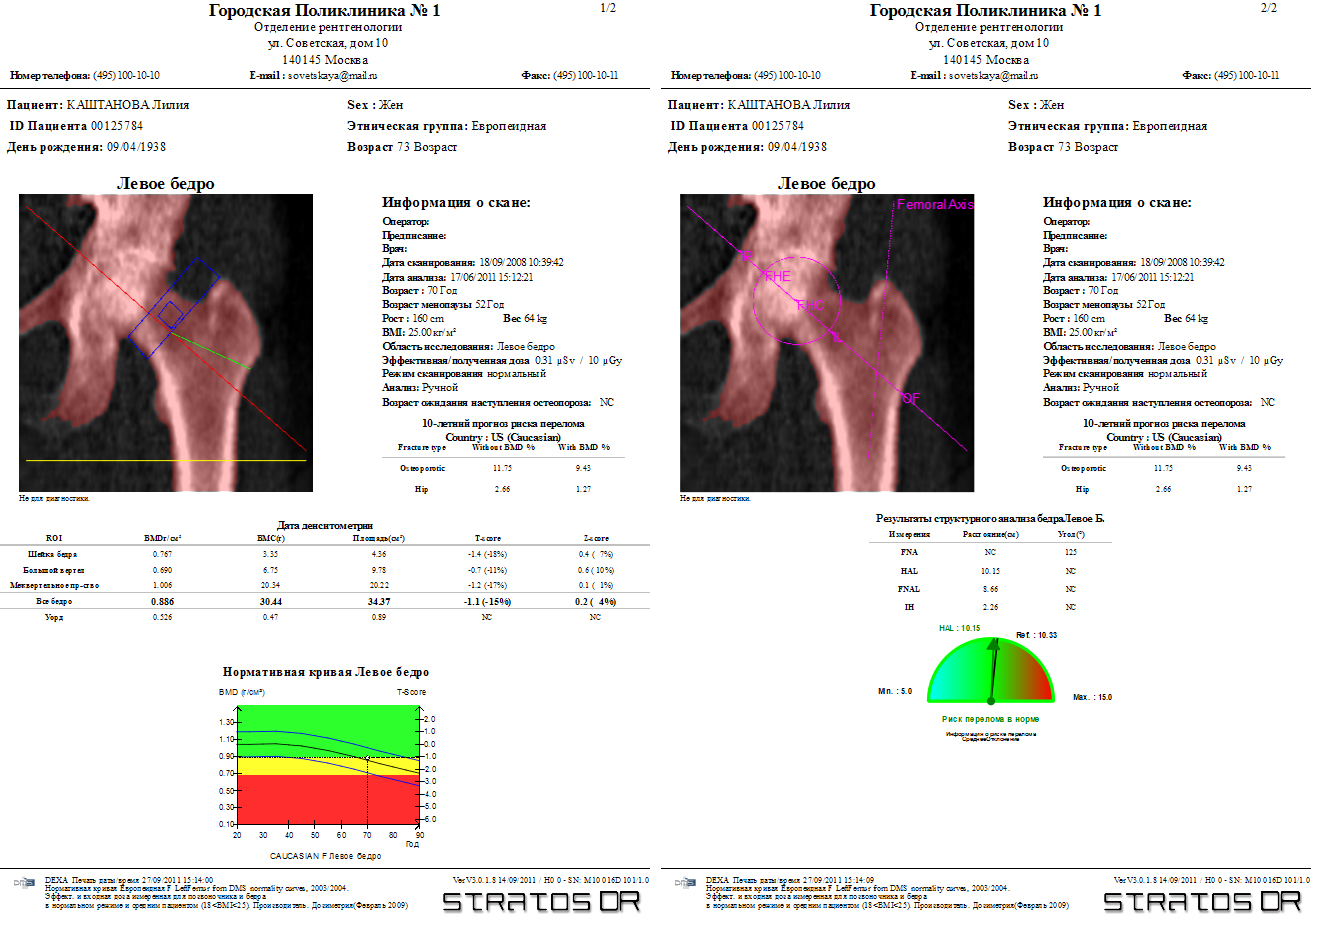

Метод DXA, двухэнергетическая рентгеновская абсорбциометрия, или денситометрия, отражающая содержание гидроксиапатита на единицу поверхности костной ткани (двойная энергия), корректирует рассеивающие эффекты двумерного сенсора. Методика двухэнергетической рентгеновской абсорбциометрии признана «золотым стандартом» в диагностике, поскольку она сочетает в себе ряд выгодных качеств; возможность исследования осевого скелета, хорошая чувствительность и специфичность, высокая точность и низкая ошибка воспроизводимости, низкая доза облучения, относительная дешевизна, быстрота исследования. При латеральном сканировании позвоночника возможен автоматизированный морфометрический анализ позвонков для выявления деформационных изменений.

- Автоматический расчет: плотности шейки бедра, вертела бедра, позвоночника, предплечья и треугольника Вордса

- Автоматический и ручной выбор: области интереса (ROI)

- Цветная распечатка отчета: (плотность кости + опорный график)

- Оценка: предполагаемой стадии остеопороза

- Оценка: риска перелома